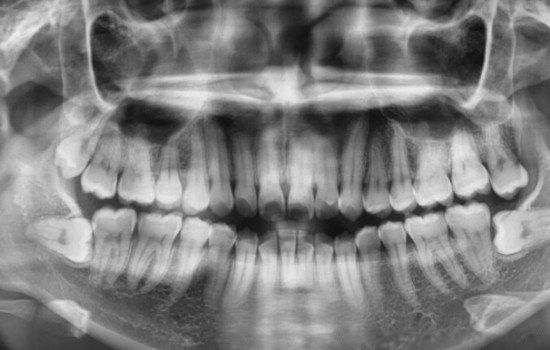

拔智齿会很疼吗 把智齿拔掉会瘦脸吗

智齿是很多人都会存在的一种牙齿问题现象,对于智齿最好的解决方法就是拔掉,但是网上一直都有拔智齿会很疼吗,把智齿拔掉会瘦脸吗说法。的确是有一些人出现了问题,例如干槽症,这让一些人苦不堪言,旦其实这是因为拔完之后一些事情没有注意好,或者没有去正规医院导致的。